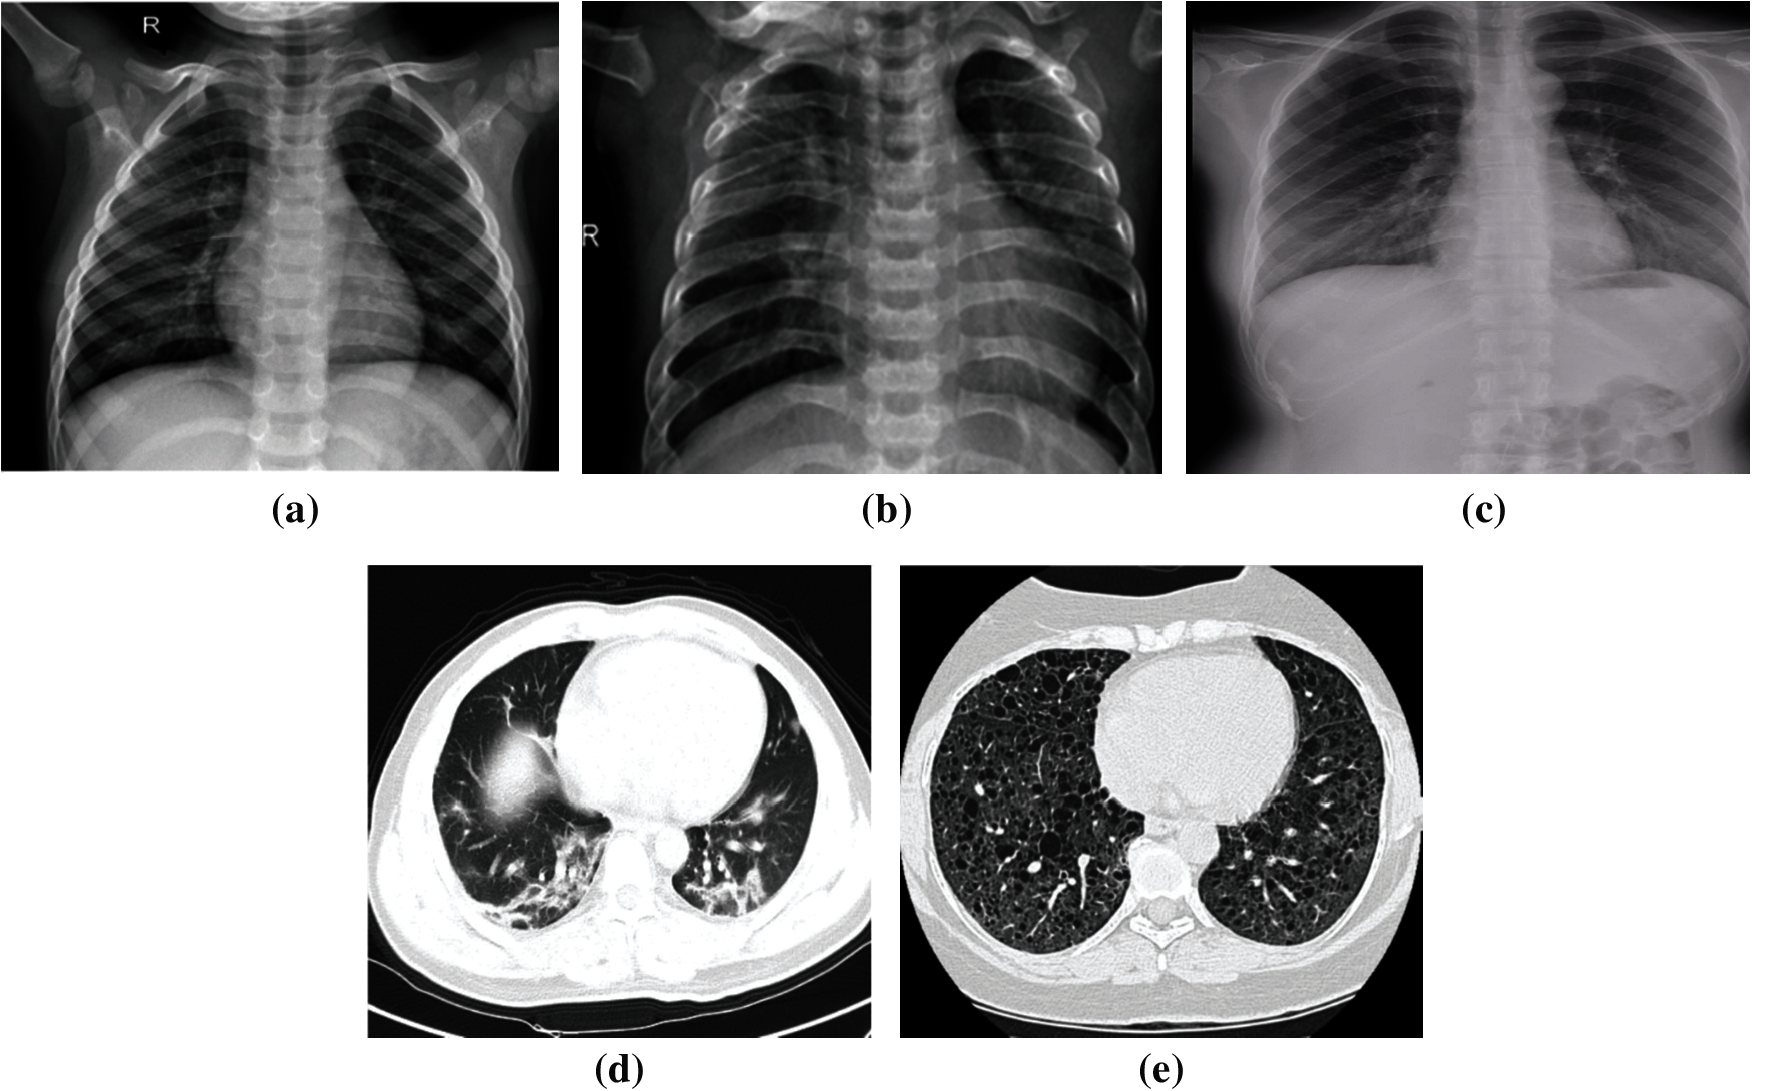

For data splitting, we adopted different ratios for training and testing (80%:20%, 70%:30%, and 60%:40%), to ensure that the models work well in different scenarios. We guarantee that the medical images selected for cross-validation are not utilized throughout the training step to execute multi-class and binary classification, effectively. Furthermore, it is noticed that the utilized X-ray dataset is imbalanced. Indeed, 46.1% of the images represent the pneumonia class, 41.4% of the images represent the normal class, and 12.5% of the images represent the COVID-19 class. The dataset imbalance problem causes over-fitting. To solve this problem, we used a dropout strategy with all employed TL models. On the other hand, the utilized CT dataset is balanced. Samples for the utilized medical images are demonstrated in Fig. 2.

Figure 2: Samples of chest X-ray and CT scans (a) Normal X-ray. (b) Pneumonia X-ray. (c) COVID-19 X-ray. (d) COVID-19 CT (e) Non-COVID-19 CT